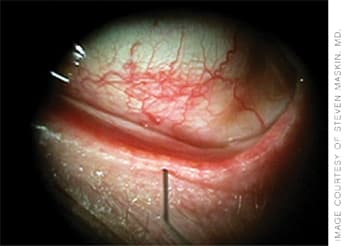

A 2-mm probe almost fully inside the meibomian gland, re-establishing patency of the duct.